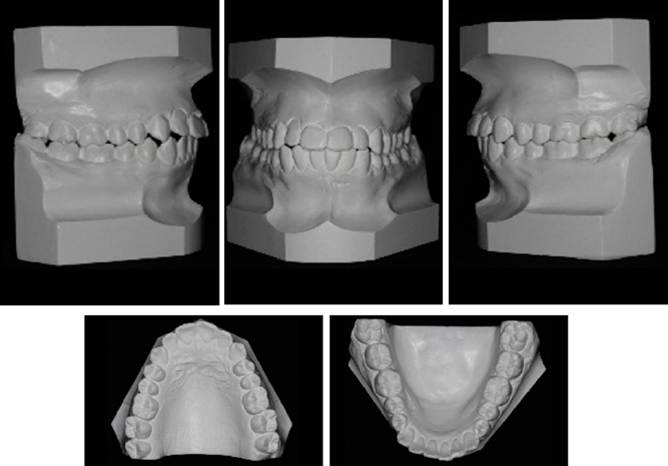

Paciente masculino de 21 años se presentó a la clínica de la Especialidad de Ortodoncia de la Escuela Nacional de Estudios Superiores Unidad León, UNAM. El motivo de consulta fue que sus dientes superiores se encontraban "muy inclinados hacia enfrente". Al analizar la historia clínica y toma de registros fotográficos (Figura 1), imagenológicos (Figura 2) y de modelos de estudio (Figura 3), se diagnosticó lo siguiente: Clase I esquelética, mesofacial, con crecimiento neutro, presencia de todos los dientes erupcionados, clase I molar bilateral, clase II canina derecha y clase I canina izquierda, con apiñamiento leve superior e inferior, protrusión y proclinación de incisivos superiores e inferiores, múltiples giroversiones; con perfil facial recto con proquelia inferior y escalón labial ligeramente negativo. Sin alteraciones ni patologías en la función del aparato estomatognático. El objetivo del tratamiento fue aliviar apiñamiento superior e inferior; corregir la proinclinación y la protrusión de los incisivos superiores e inferiores; distalizar arcada superior e inferior con intrusión del segmento posterior y retroclinación del segmento anterior; conservar la clase I molar, lograr clase I canina bilateral, y retruir el labio inferior.